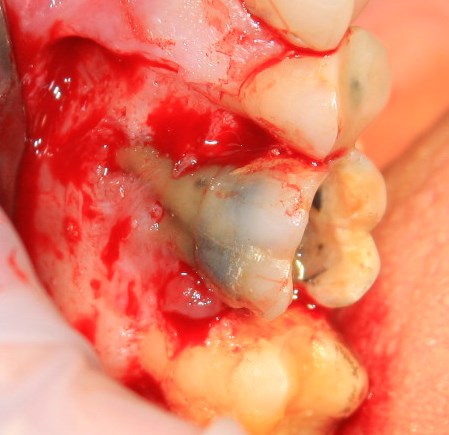

Немедленная имплантация — оптимальное решение в любой клинической ситуации